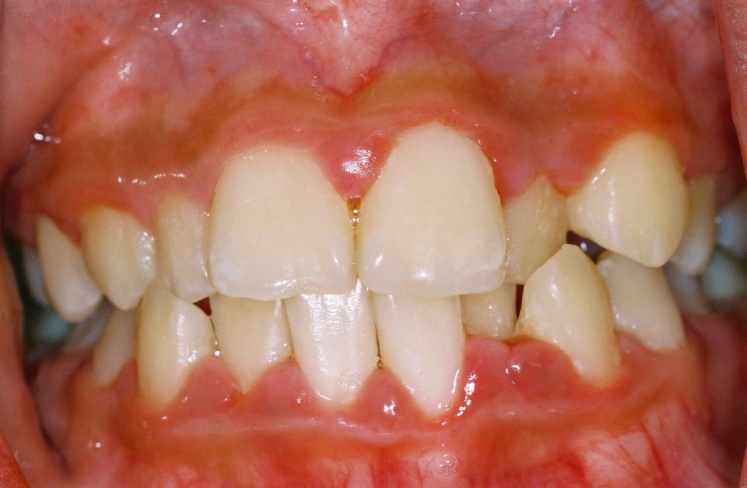

A patient with generalised gingivitis. Note the red, swollen, inflammed gum tissues around the teeth. These gums bleed easily on brushing.